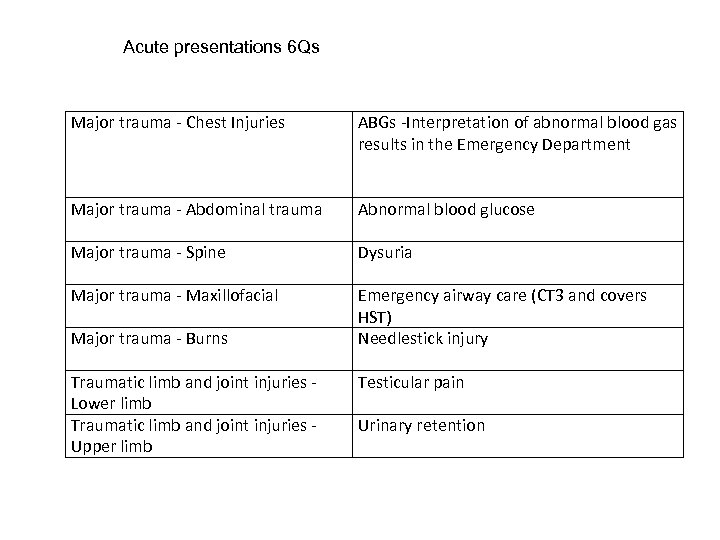

Acute presentations 6 Qs Major trauma - Chest Injuries ABGs -Interpretation of abnormal blood gas results in the Emergency Department Major trauma - Abdominal trauma Abnormal blood glucose Major trauma - Spine Dysuria Major trauma - Maxillofacial Emergency airway care (CT 3 and covers HST) Needlestick injury Major trauma - Burns Traumatic limb and joint injuries - Lower limb Traumatic limb and joint injuries - Upper limb Testicular pain Urinary retention